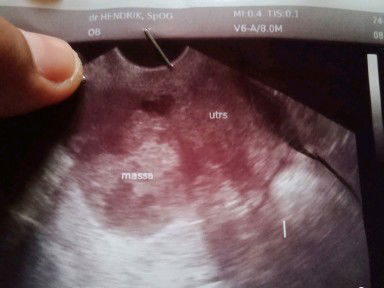

USG kmaren Dokter bilang sya ga hamil Dan ada benjolan di perut sya Dan sya nanya benjolan apa dok Malah dokter balik nanya ke saya ??♀️??♀️ Kan sya ga tau itu benjolan apa

di USG ga hamil

Tanggal 29-3-2020 pertama tespek 5x tespek hasilnya positiv Priksa bidan katanya baru 5minggu Dan sya tunggu usia kandungan ku 8 Minggu lebih sya USG dan dokter bilang sya ga hamil Sempet di situ sy di tespek LG dan hasilnya negativ Dan dikter bilang ada benjolan di perut sya Namanya massa dokter bilang seperti tumor tp blum pasti !!! Sya harus gimnh Bun???